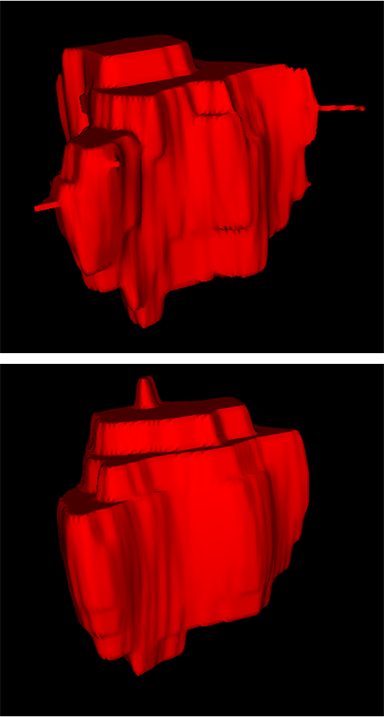

Comparison with ground truth. Some predicted results of MMFNet are shown in 2D images and 3D images in Figure 7 and Figure 8. As shown in these figures, although the shape and size of NPC are varied from each other, MMFNet can still accurately determine the regions of NPC and obtain the accurate contours of tumors. Through analyzing 2D images in figure 7, MMFNet has a capacity to fuse multi-modality MRI to reduce the confusion brought by intensity’ similarity between nearby tissues and NPC. The values of , and of MMFNet are shown in Table 1. MMFNet can reach the best results with , and .

Comparison with related works. Table 1 reports the values of , and for different methods. Predicted masks of different methods are illustrated in Figure 9 and Figure 10, which respectively present results in 2D and 3D images. Through comprehensively analyzing these results, the proposed MMFNet actually have the following properties:

(i) It directly fuses 3D MRI images rather than 2D slices. Thus, it can effectively use meaningful information from neighboring slices of MRI to realize NPC segmentation. As shown in Table 2, MMFNet can bring , and improvements in and compared to the best method based on 2D images (Multi-modality patch-based CNN). And Figure 10 shows that 3D-based methods have less isolated regions (false positives) than 2D-based ones.